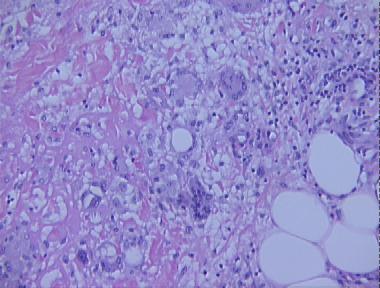

erythema nodosum

Histologic Features